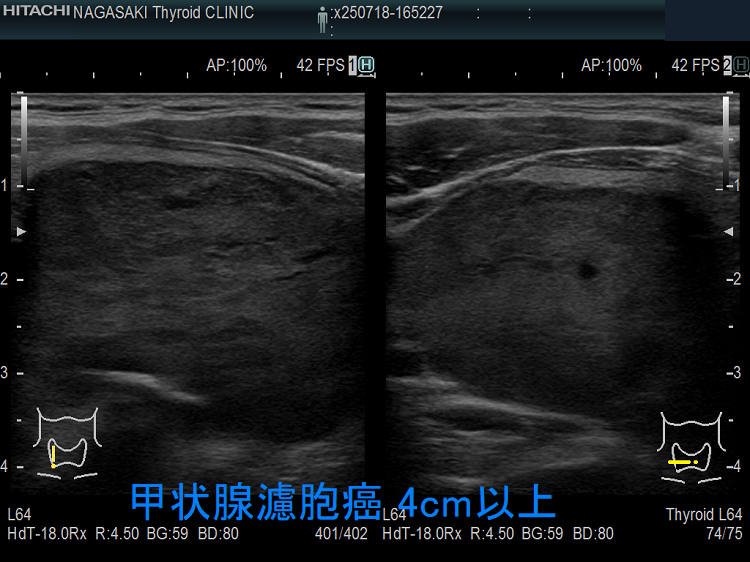

巨大濾胞癌 超音波(エコー)画像です。1画面に入りきらないため、軽く4cmは超えています。気管を圧迫し、良性濾胞腺腫では少ない石灰化を認め、たとえ穿刺細胞診で正常・良性、擬陽性であっても一目瞭然、甲状腺濾胞癌です。

甲状腺濾胞癌 4cm以上;誤嚥・嚥下困難症状あり。エコーでは低エコー、エラストグラフィーでJTEC パターン2。穿刺細胞診ではクラス3a 偽陽性。切除標本では血管浸潤を4カ所以上認めた。